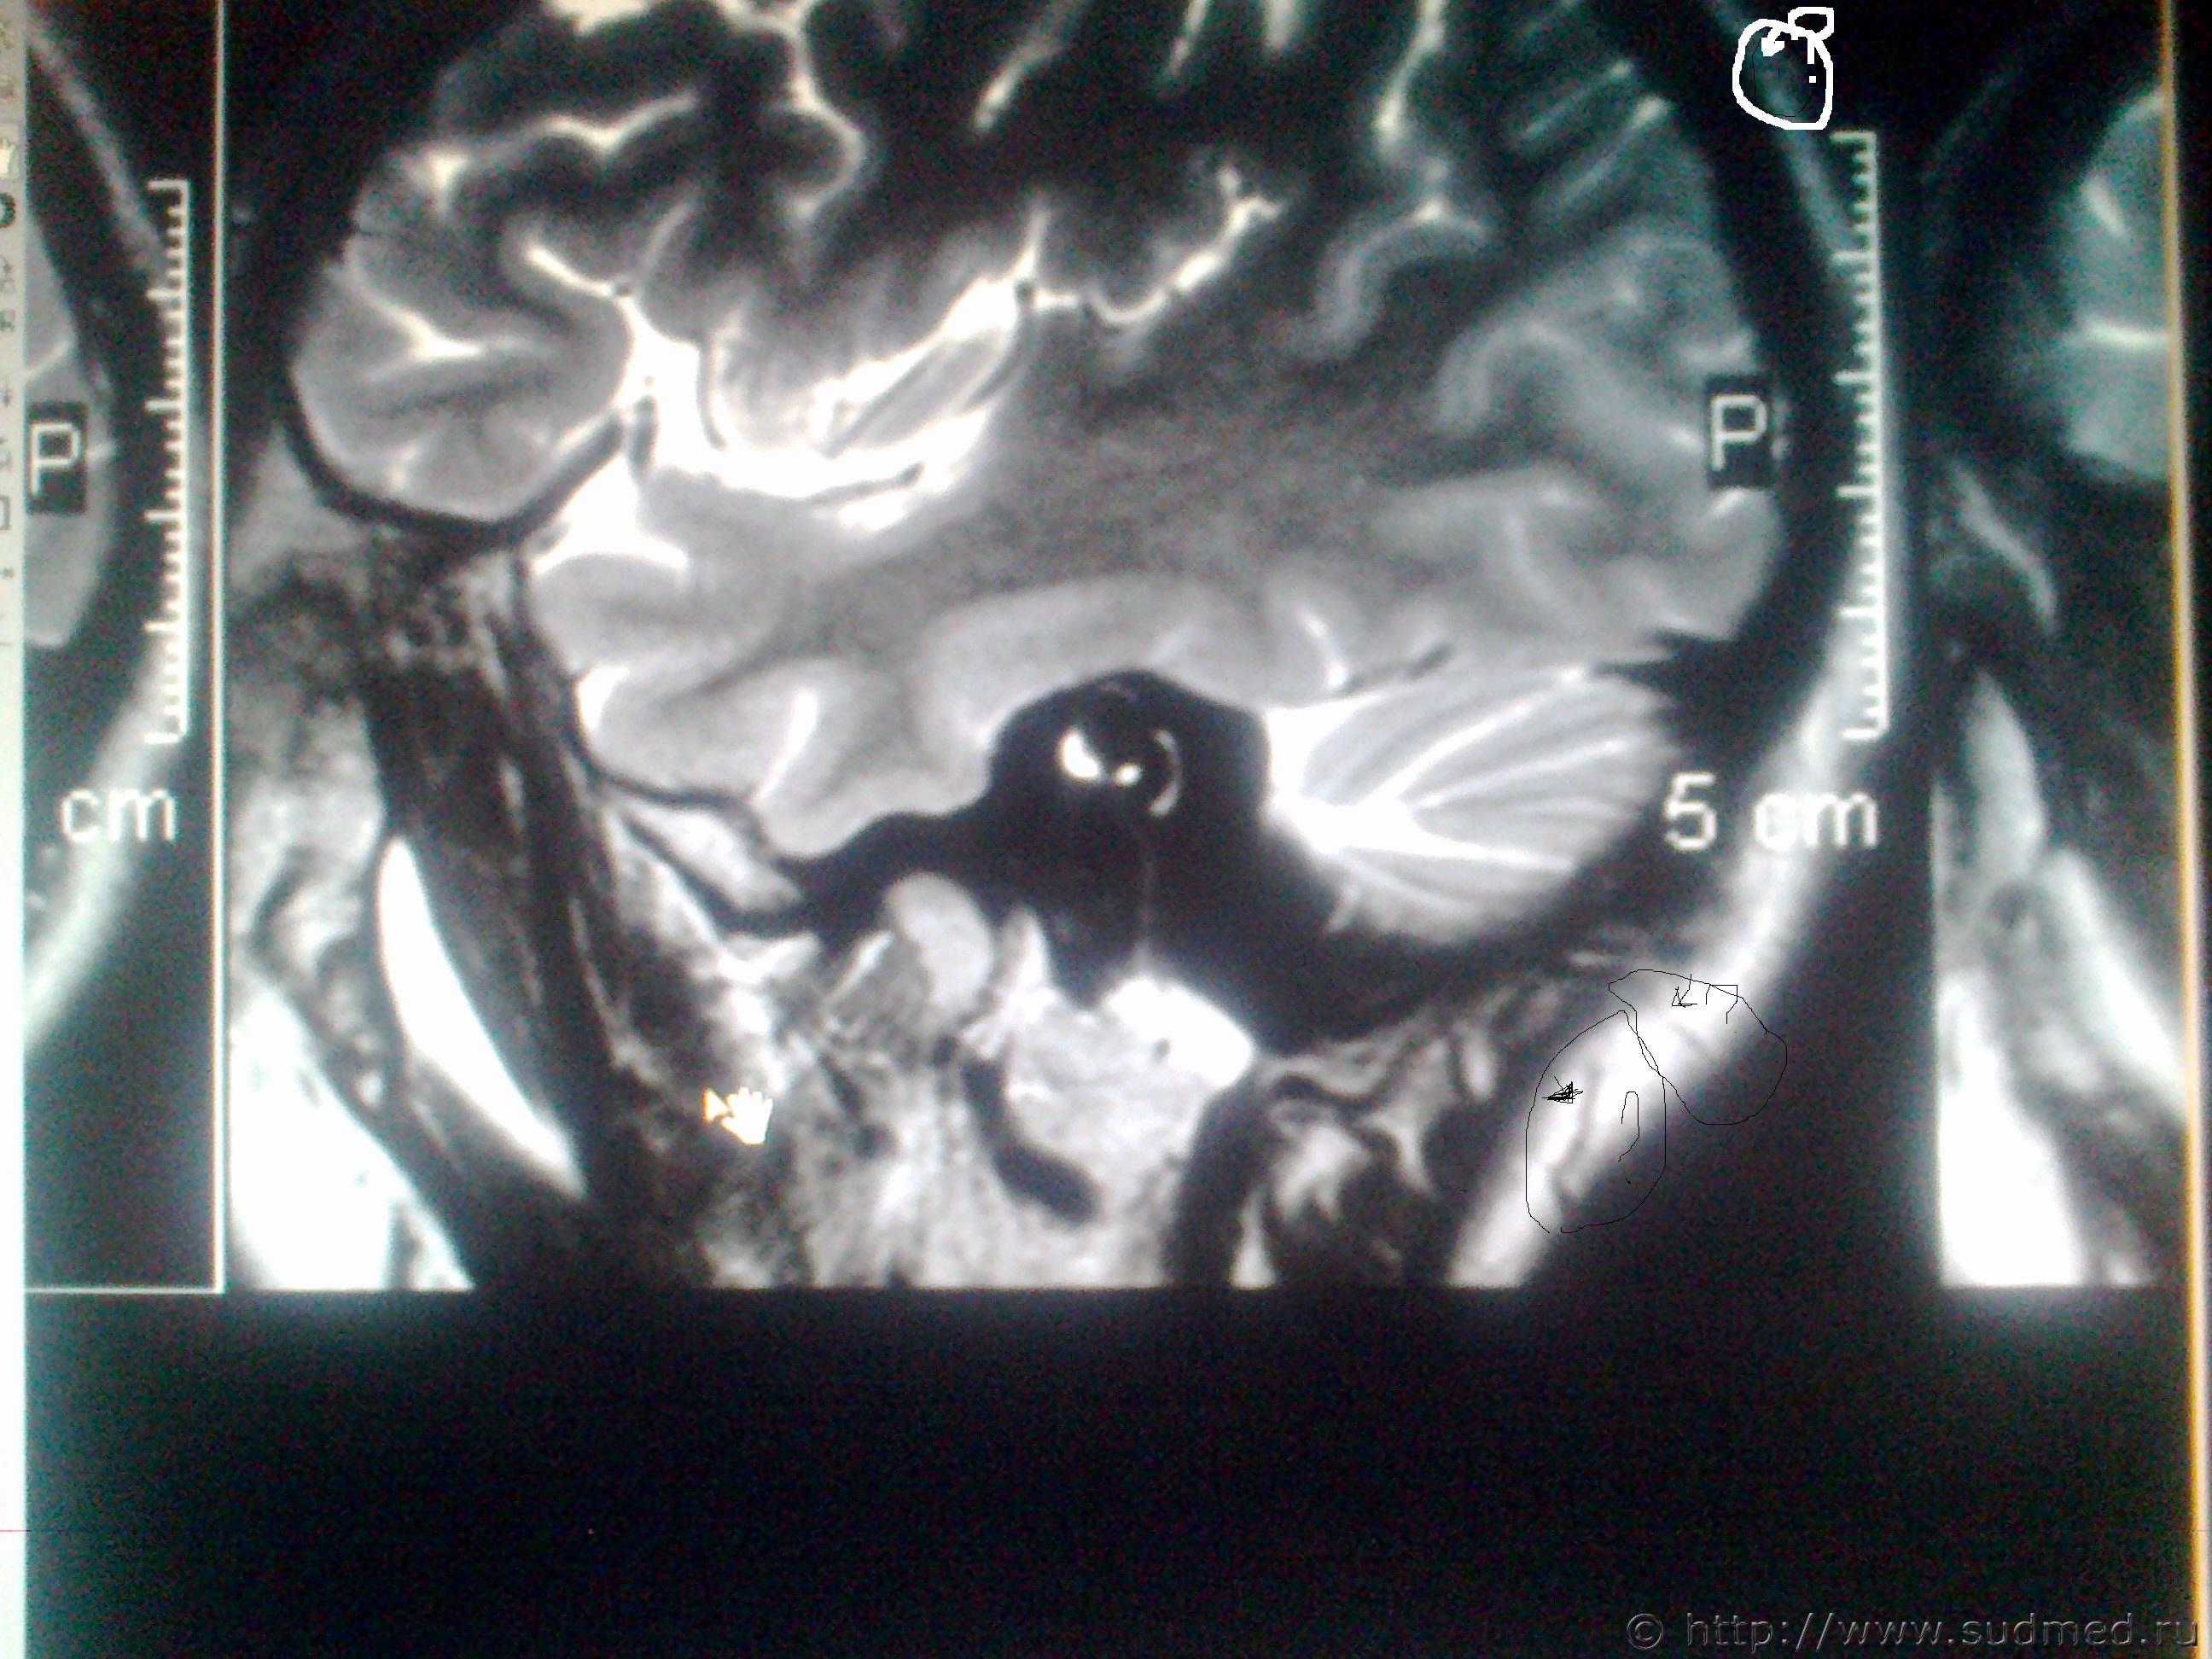

ув. специалисты! Мне оч. хочется узнать ваше мнение, что показано на мрт снимках в мозгу и на костной ткани, интересующие места обведены. Есть ли трещины на костях черепа или это шов и что значит чёрное- белое пятно на снимке мозга?

Светичок! Надо показать сами эти снимки специалисту по МРТ (на пленке и/или на электронном носителе. На эл.носителе даже лучше, т.к. на пленке могут быть распечатаны, к примеру, 30 сканов, а, фактически, их 150 было выполнено и все они могут быть представлены Вам на диске или на флешке). Присланное Вами хуже по качеству, чем снимки, которые есть фактически и, на этом форуме, насколько мне известно, нет врачей имеющих сертификат по специальности"Рентгенология" и дополнительную специальную подготовку по ядерно-магнито-резонансной томографии. Поищите какой-нибудь форум рентгенологов, вероятно, там смогут дать более компетентные комментарии. Насколько я разбираюсь в МРТ (немножко): на снимках №1, 2 и 3 - вероятнее всего, ликворная киста. Возможно, это вариант развития, возможно, след от давно регрессировавшей (прошедшей, рассосавшейся) гематомы. В любом случае, даже если это изменение имеет посттравматическое происхождение, то травма была давно (месяцы или годы назад), на что указывает отсутствие признаков внутричерепной гематомы, перифокального отека вещества головного мозга. Только по этим снимкам ни один специалист не сможет серьезно и аргументированно доказать, что это: 1.именно последствие травмы и ни что другое, 2.точно установить дату этой предполагаемой травмы. (Просьба не путать специалиста с шарлатаном, который, "все что угодно за ваши деньги" - в суде такое "заключение" окажется несостоятельным). На снимках №4 и 5 - шов между затылочной и теменными костями, №6 - каналы диплоэтических вен (вены, проходящие сквозь кости черепа. Они извитые, а перелом, в такой проекции выглядит как прямая линия, перпендикулярно и косо-перпендикулярно пересекающая кость свода черепа). МРТ - неоптимальный метод для оценки состояния костей свода черепа (МРТ - великолепный метод для оценки состояния мягких тканей). Гораздо лучше - обычная рентгенография костей свода черепа. Желательно,сделанная на современном цифровом рентгеновском аппарате. Желательно - полипозиционная (т.е. не только стандартные снимки в прямой и одной из боковых проекций, а, в данном случае - прямая проекция,правая и левая боковые проекции, контактная рентгенограмма затылочной кости и, возможно, снимок с выведением места предполагаемого перелома в краеобразующую зону. Тогда на 100% будет понятно,что это такое. Вероятно, на 100% будет понятно уже на стадии рентгенограмм в прямой и боковых проекциях. Грамотный рентгенолог знает все это лучше, чем я тут написал). Можно, конечно, сделать мультиспиральную компьютерную томографию /МСКТ/ в костном режиме с 3-D реформацией изображения,однако, лучевая нагрузка будет больше, а информативность - сопоставимая. Если в итоге найдется что-то похожее на посттраматические изменения, то нужно будет провести исследование всех рентгенограмм, которые выполнялись непосредственно после конкретной травмы, если когда-то до неё делались рентгенограммы, МРТ, КТ головы - их тоже. Это уже задача судебно-медицинской экспертизы. + будут учитываться данные медицинских карт и прочие документы о лечении после этой травмы, о состоянии здоровья до неё и т.п., т.к. перелом кости/костей свода черепа, внутричерепная гематома протекают с весьма выраженной клинической симптоматикой (от чего-то "легкого" и похожего на "сотрясение головного мозга" до тяжелых невропатологических проблем).